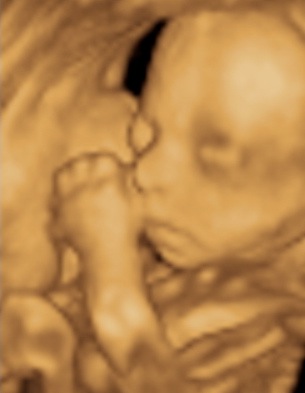

A 3D-s babafotok meg mindig lenyugoznek, nem birok betelni veluk. SZomoruan olvasom, hogy mennyi aprobb-nagyobb kellemetlensegetek van, de szerintem mindenki nagyon szuperul halad, ugyesek vagytok...le a kalappal foleg a dolgozok, vagy mar babasok elott! majd most teszek fel kepeket es is Azzurrarol, bar mar tobb, mint 5 hete keszultek, de ujabbak mar nem lesznek, es mivel kimaradtam abban az idoszakban, most potolom. Az tuti, hogy ezentul mindenkinek javasolni fogom a 4D-t ilyen koran is (22+1 hetesen voltunk), mert bar csimota ducibb volt az atlagnal es mar akkor volt rajta jo adagnyi izom (ez is a napi 1 l tej

), de egy sovanyabb baba is csodaszep szerintem...mindent el lehet mondani, csak azt nem, hogy csontkollekciok lennenek. Osszessegeben ugy nez ki, hogy ram hasonlit, de a szemoldokcsontja es a szaja az egy az egyben a parome...szerencsere...neki az sokkal szebb...remelem, haj-ugyben is ra ut majd